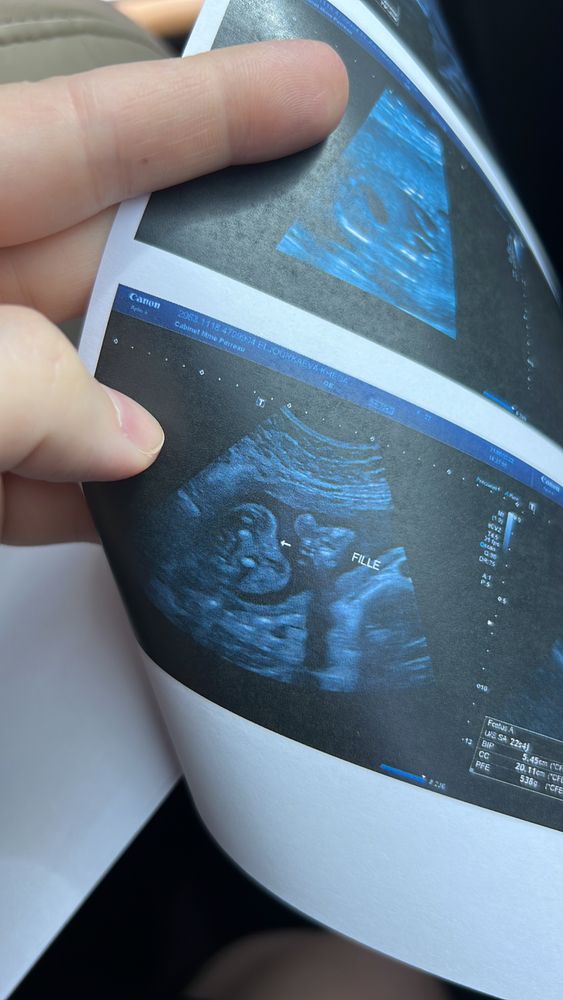

Говорит девочка, но как то странно))) где 2 полосы параллельные? Кофейное зёрнышко?

Нее это девочка

Был бы мальчик - было бы хорошо видно пенис и мошонку. Их нет, значит девочка. Полосок может и не быть видно.

Ну мошонки тут точно нет, так что выбор невелик!

Девчоночка ага.

Девочка❤️

Париж, если увеличить там видно кофейное зёрнышко